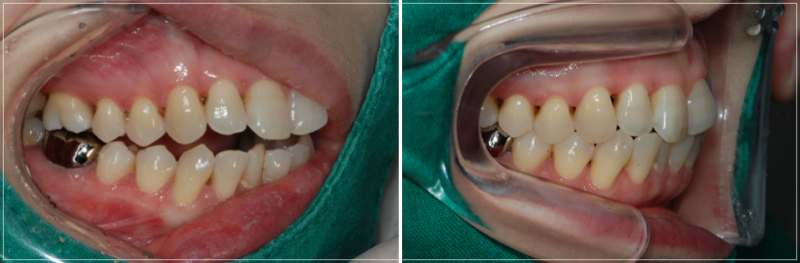

입이 안 다물어지는 문제를 해결한 모습

태어날때 부터 생긴 문제로 인한

개방교합은 보통 치아 교정을 통해

해결하면 된다고 생각하시는 분들이 많은데,

만일 턱관절 질환으로 인해 생긴 경우

잘 모르고 치아 교정부터 진행하게 되면

턱이 불안정한 상태에서 치아를

움직이게 되기 때문에 오히려 질환을

악화시키거나 무리한 치아 이동으로 인해

개방교합이 다시 생겨나는 등 문제가

발생할 수 있어서 주의가 필요합니다.